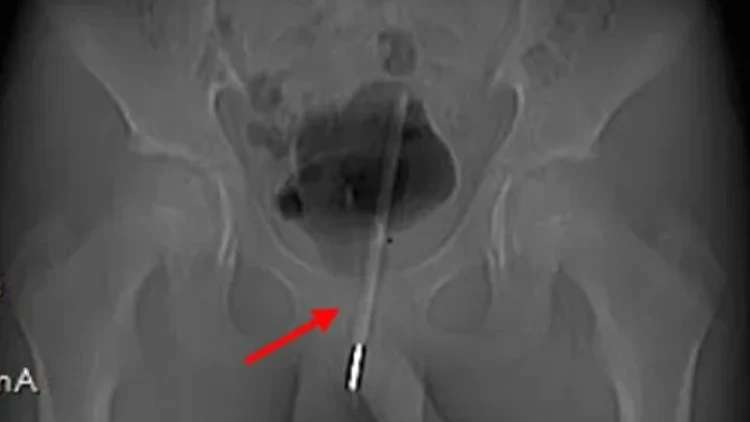

צילומי הרנטגן הראו שהמדחום נמצא כל כך עמוק בדרכי השתן, שהוא נכנס לתוך שלפוחית השתן של הילד.